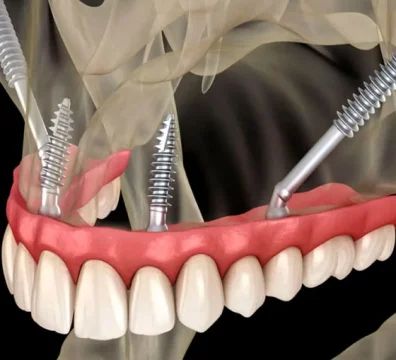

Los implantes pterigoideos son implantes dentales largos que se colocan en la apófisis pterigoidea , una zona ósea profunda y muy densa situada en la parte posterior del maxilar superior. Esta región ofrece una excelente estabilidad primaria , incluso en pacientes con gran pérdida ósea.

A diferencia de los implantes tradicionales, los implantes pterigoideos se colocan con una inclinación específica , anclándose en hueso de alta calidad y permitiendo la colocación de prótesis fijas sin necesidad de regeneración ósea previa.

Permiten implantes dentales fijos cuando no hay hueso

Evitan injertos óseos y elevación de seno maxilar

Alta estabilidad primaria

Posibilidad de dientes fijos en el mismo día en muchos casos